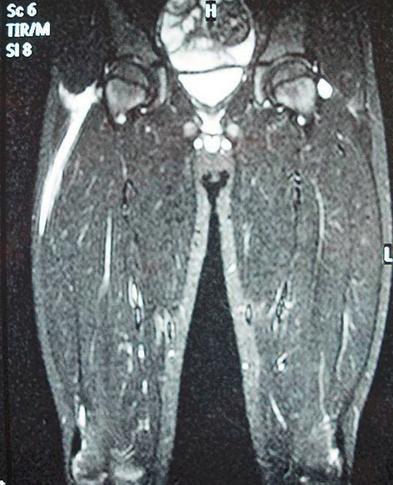

坏死性筋膜炎又称食肉菌感染,是一种广泛而迅速的皮下组织和筋膜坏死为特征的软组织感染,是一种非常罕见的感染性疾病。食肉菌专“吃”脂肪和筋膜,如果不及时清除,短时间内患者就会发展为中毒性休克、多器官功能衰竭甚至死亡。本病是多种细菌的混合感染,其中主要是化脓性链球菌和金黄葡萄球菌等需氧菌。本病感染只损害皮下组织和筋膜,不累及感染部位的肌肉组织是其重要特征。

(1)片状红肿、疼痛:早期皮肤红肿,呈紫红色片状,边界不清,疼痛。此时皮下组织已经坏死,因淋巴通路已被迅速破坏,故少有淋巴管炎和淋巴结炎。感染24h内可波及整个肢体。个别病例可起病缓慢、早期处于潜伏状态。受累皮肤发红或发白、水肿,触痛明显,病灶边界不清,呈弥漫性蜂窝织炎状。

(4)奇臭的血性渗液:皮下脂肪和筋膜水肿、渗液发黏、混浊、发黑,最终液化坏死。渗出液为血性浆液性液体,有奇臭。坏死广泛扩散,呈潜行状,有时产生皮下气体,检查可发现捻发音。